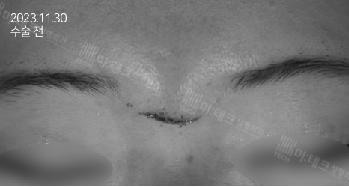

미간에 한눈에 보기에도 흉측한 상처가 생긴 상황입니다.

직각으로 찢어진 형태가 아니라 비스듬한 흉터인데 이를 beveled wound라고 합니다.

이런 상처는 좀 더 봉합에 신중을 기해야 하고,

이후 예후가 상대적으로 좋지 않기에 조기에 흉터 치료를 해 주어야 합니다.